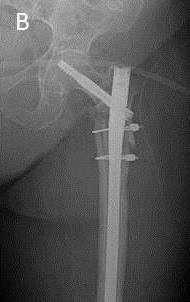

Se realizaron radiografías anteroposterior de pelvis y axial de cadera izquierda afecta, se objetivó una fractura persubtrocantérea de fémur tipo IIB de Russel - Taylor o 31-A3 de la AO (fig. 1A), conminuta, con afectación de la cortical posteromedial.

A las 48 horas del ingreso, previa valoración anestésica y estudio preoperatorio, es intervenida sobre una mesa de tracción. En primer lugar se realizó una reducción abierta de foco de fractura mediante abordaje lateral directo y fijación con dos cerclajes (para restaurar la anatomía de la cortical medial). Posteriormente se realizó una osteosíntesis percutánea con clavo  largo intramedular, tornillo cefálico deslizante y cerrojo distal dinámico.

El postoperatorio transcurre sin complicaciones, salvo un cuadro de anemización que requirió transfundir dos concentrados de hematíes. El control radiológico postquirúrgico es correcto (fig. 1B), por lo que la paciente es dada de alta en descarga (vida cama-sillón) por la inestabilidad de la fractura.